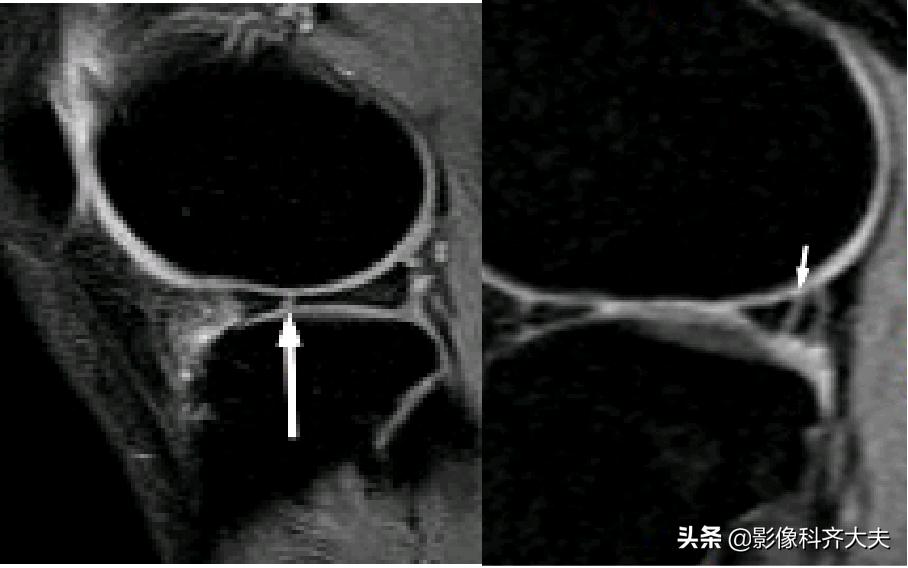

容易误诊为半月板损伤的正常解剖结构

膝横韧带:

腘肌腱腱鞘:

后股板韧带:

内侧半月板后角上隐窝: